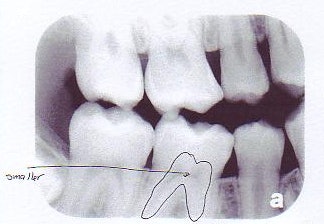

| Left, bitewing shows the large pulp typical of a 9-year-old. Right, bitewing of a 16-year-old shows a smaller pulp. | |